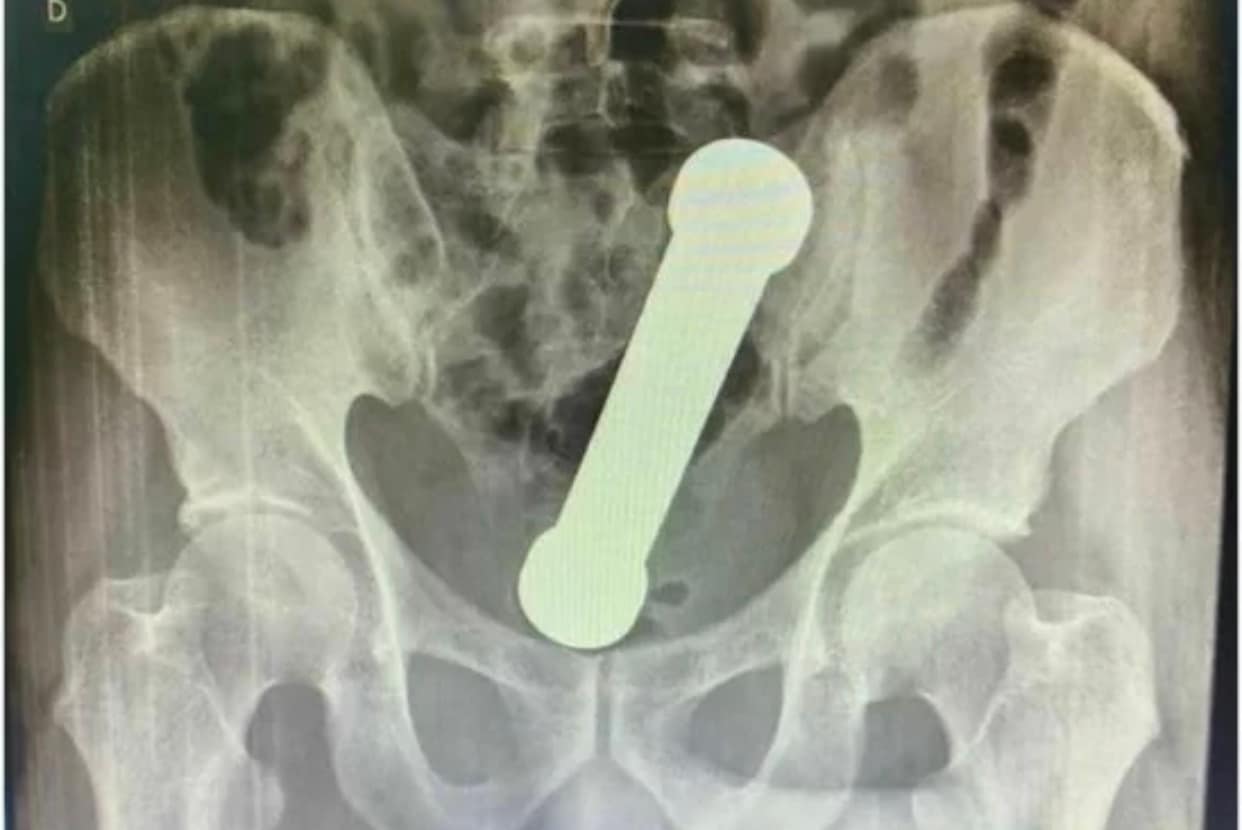

Após vários exames foi pedido uma radiografia abdominal. A radiografia revelou a presença de um HALTERE de ginástica em “localização aproximada de transição retal”

Haltere removido do ânus de homem de 54 anos